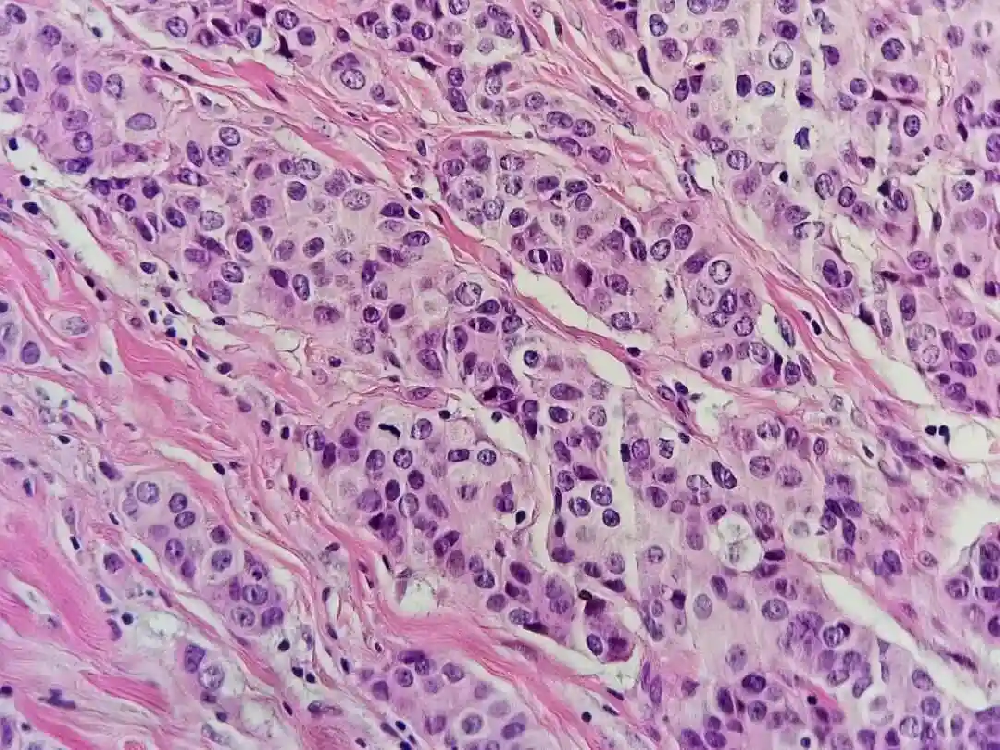

乳腺癌病理報告解讀:ER、PR、Ki-67、HER-2 等指標全解析 乳腺癌是女性常見惡性腫瘤,發病率佔全身惡性腫瘤的 7%~10%,其中免疫組化結果是核心,可明確分子類型、指導治療並提示預後。......【查看全文】